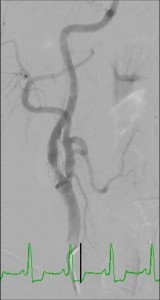

Angiography for the diagnosis of carotid artery stenosis

Angiography is the traditional ‘gold standard’ for the imaging of blood vessels. Direct angiography offers the best means for visualization of carotid artery lesions and overcomes most of the limitations that were listed for the other methods. The main disadvantages of carotid artery angiography include:

- It is an invasive procedure

- It exposes patients to ionizing radiation and contrast material

Therefore, nowadays angiography is utilized only when the non-invasive methods gave inconclusive results.